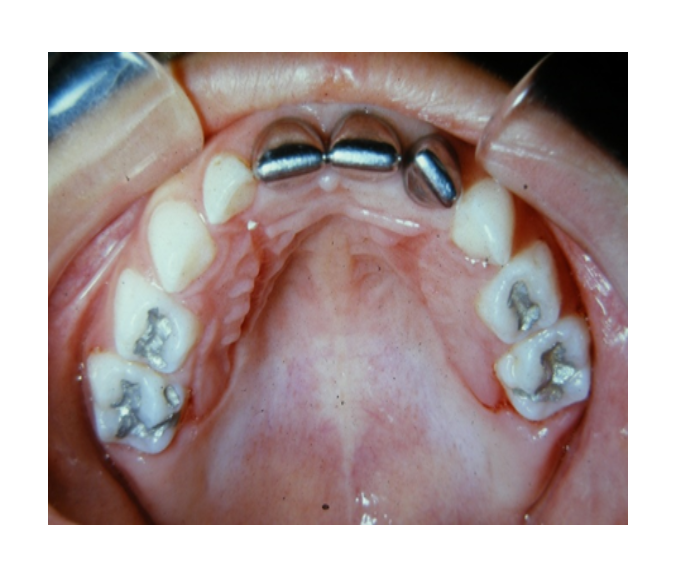

Mordida cruzada posterior bilateral